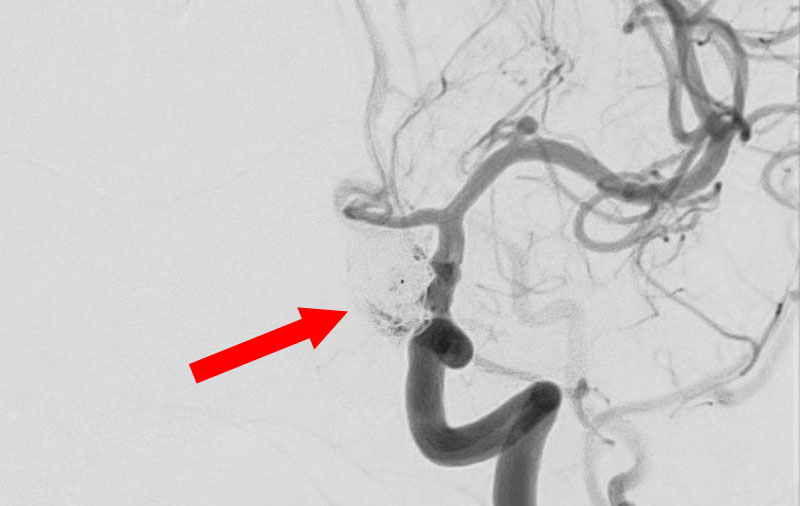

No.1593 手術中